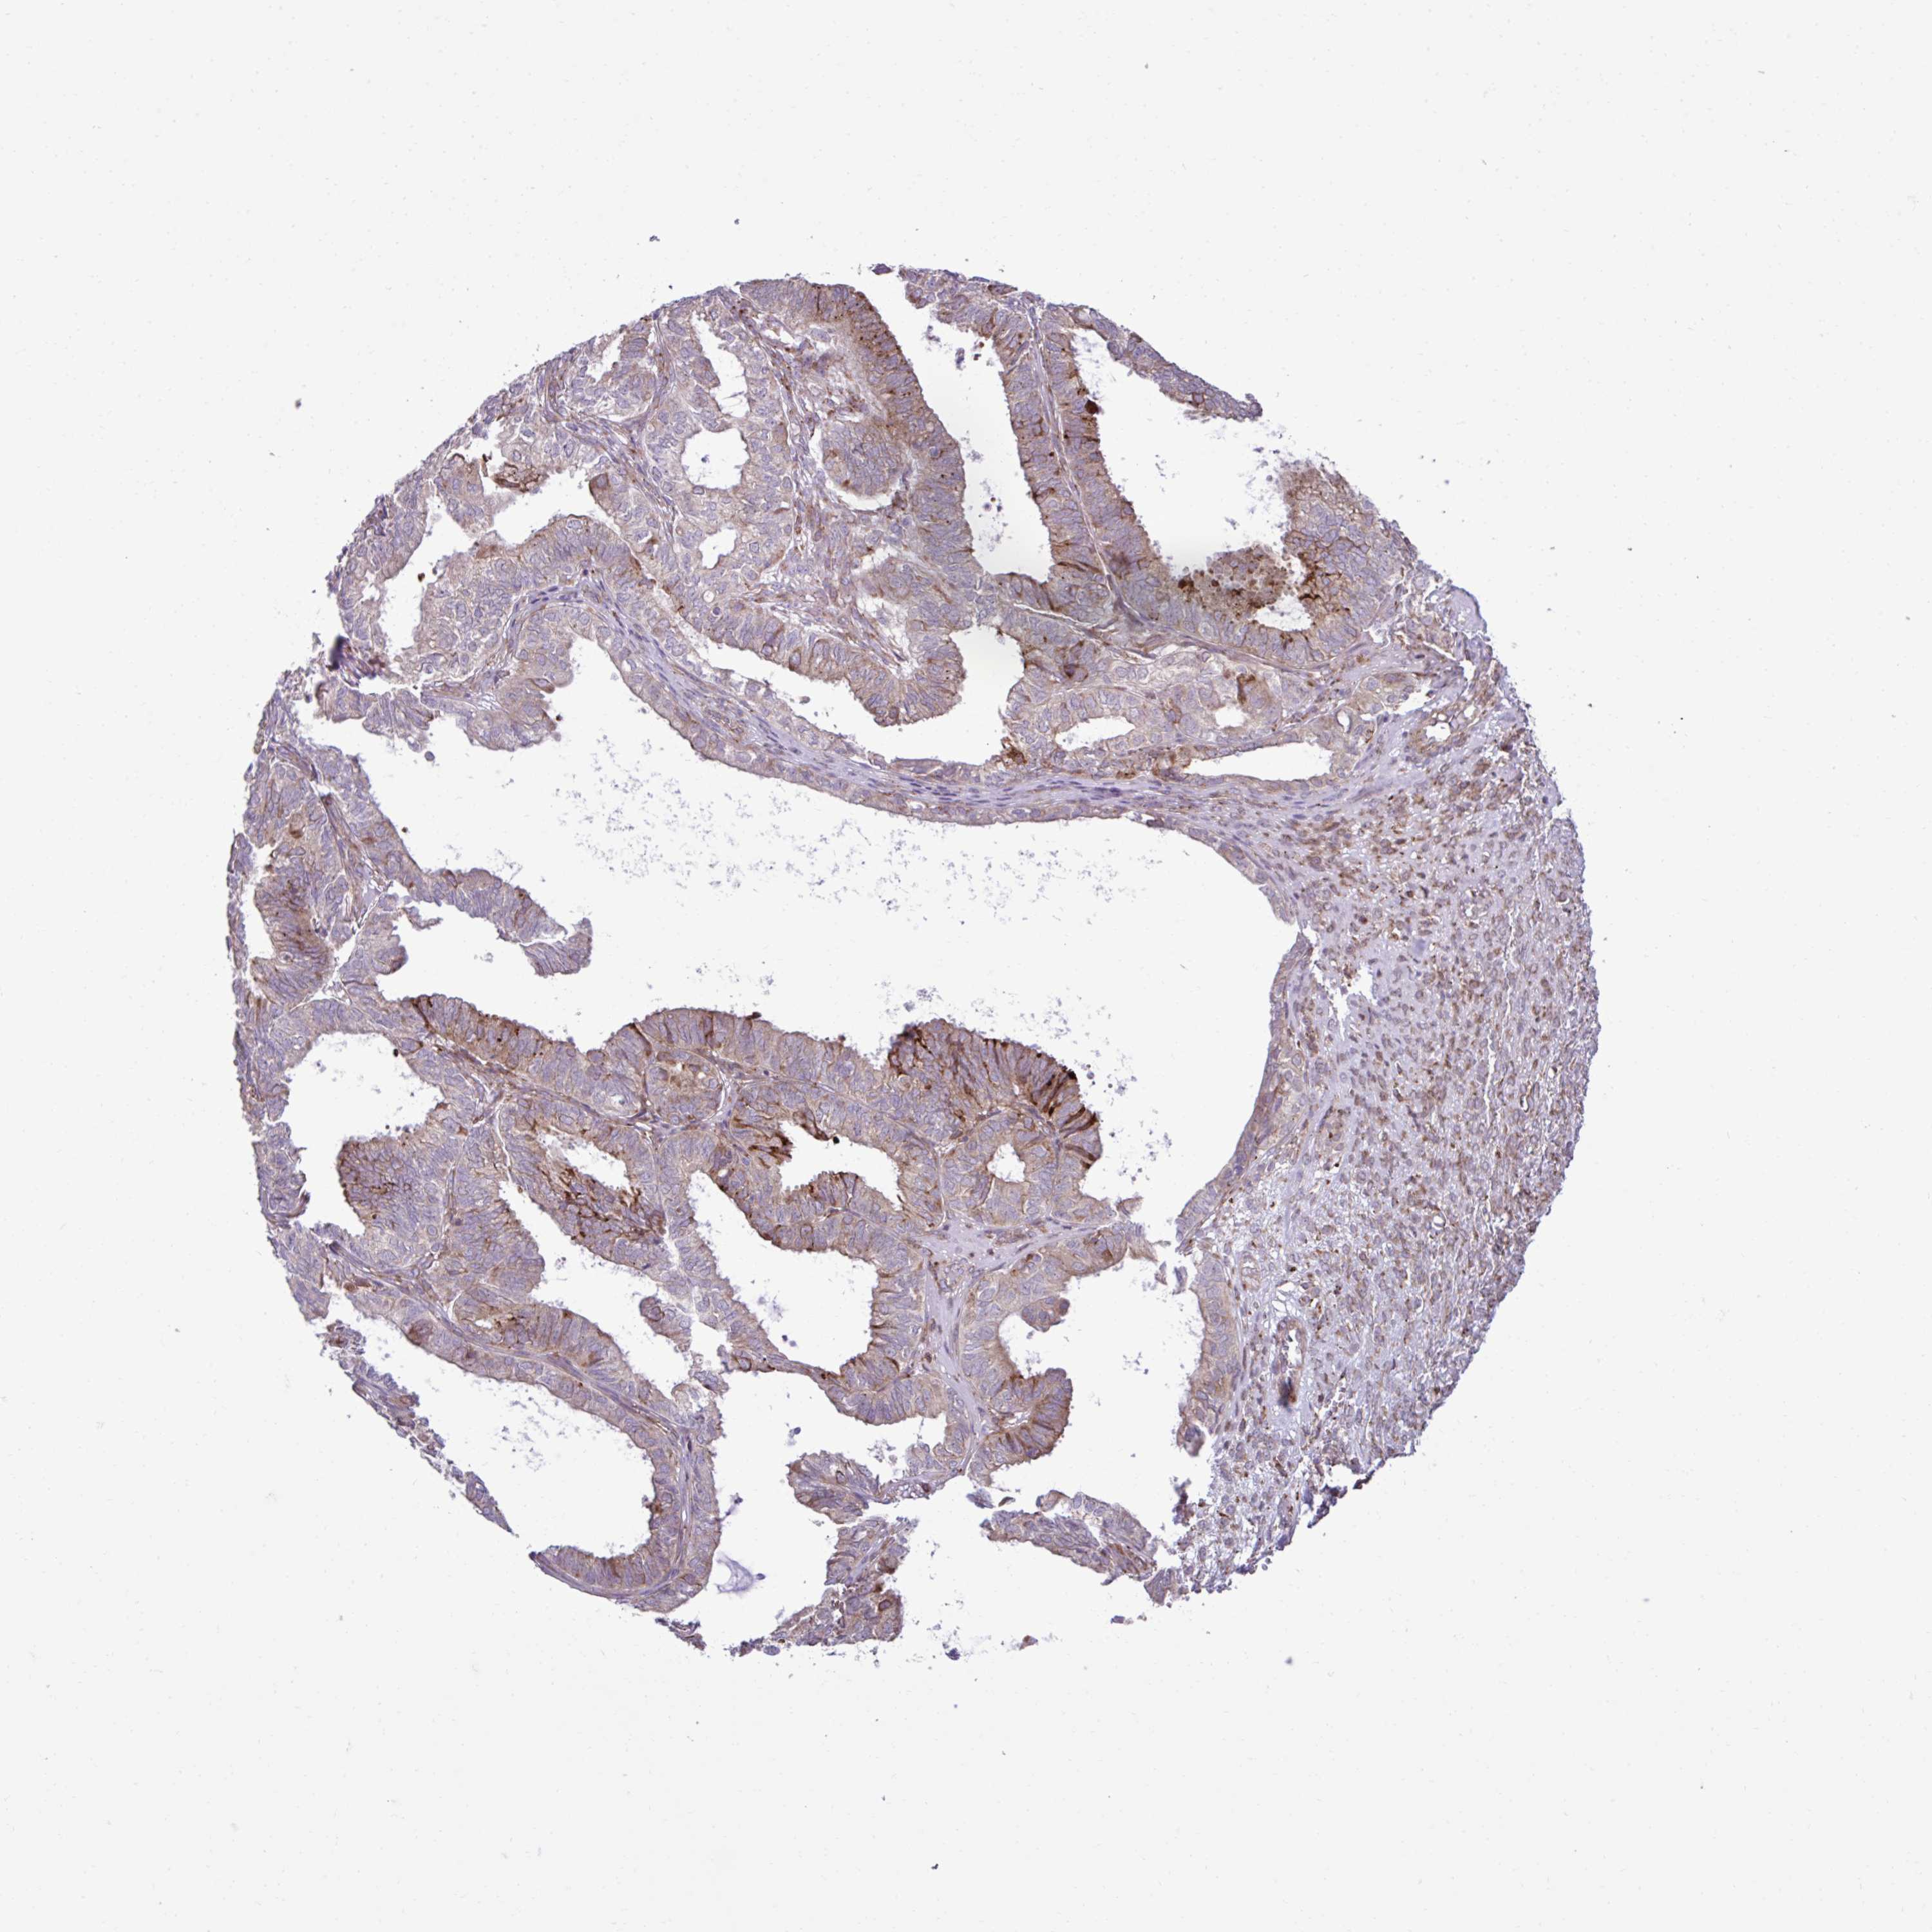

OVARIAN CANCER - Protein expressioni

A mouse-over function shows sample information and annotation data. Click on an image to view it in a full screen mode. Samples can be filtered based on level of antibody staining by selecting one or several of the following categories: high, medium, low and not detected. The assay and annotation is described here.

Note that samples used for immunohistochemistry by the Human Protein Atlas do not correspond to samples in the TCGA dataset.

Antibody stainingi

Antibody staining in the annotated cell types in the current human tissue is reported as not detected, low, medium, or high, based on conventional immunohistochemistry profiling in selected tissues. This score is based on the combination of the staining intensity and fraction of stained cells.

Each image is clickable and will lead to virtual microscopy that enables deeper exploration of all samples and also displays staining intensity scores, fraction scores and subcellular localization as well as patient and tissue information for each sample.

Antibody HPA058455

Antibody HPA061230

Staining

High

Medium

Low

Not detected

Intensity

Strong

Moderate

Weak

Negative

Quantity

>75%

75%-25%

<25%

None

Location

Nuclear

Cytoplasmic/membranous

Cytoplasmic/membranous,nuclear

Cystadenocarcinoma, serous, NOS

Cystadenocarcinoma, mucinous, NOS

Carcinoma, endometroid